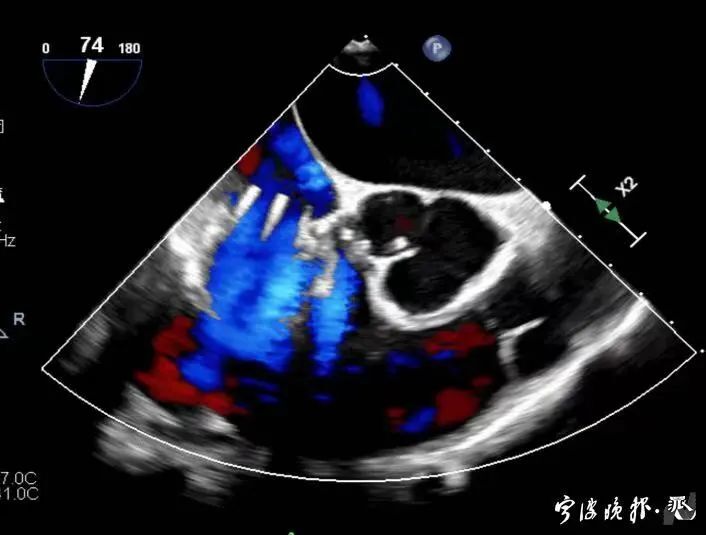

術后食道心超示三尖瓣反流消失

得知可以微創手術,陳大爺一家決定放手一搏。寧波市醫療中心李惠利醫院心臟瓣膜中心團隊反復就術前準備、手術步驟及術后可能出現的各種情況做了預案。3月4日,陳大爺的手術成功進行,術中得到LuX-Valve經導管三尖瓣置換術原創團隊,上海長海醫院陸方林主任團隊的鼎力支持,術后陳大爺的心臟三尖瓣反流立即消失。術后瓣膜中心CCU(心臟監護)團隊和心內科團隊迎接一個又一個右心瓣膜置換后的血流動力學改變等帶來的挑戰,克服種種難關,二周后患者進入早期心臟康復。目前陳大爺已經順利出院,沒有胸悶氣急,生活自理,精神狀態也很好,瓣膜中心團隊也在對他持續隨訪中。